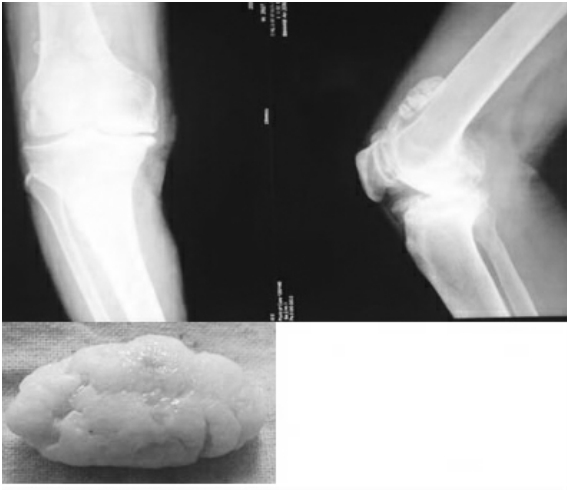

1.10.7 膝关节内游离体

膝关节内游离体较多见,主要来源于剥脱性骨软骨炎、滑膜骨软骨瘤病、骨赘、关节面骨折、损伤的半月板。游离体可为纤维蛋白性、纤维性或骨软骨性。纤维蛋白性游离体可继发于关节内出血,血凝块极化构成。纤维性游离体常为自身脱落的肥大滑膜绒毛。软骨性游离体主要来自创伤或各种病理情况,如滑膜骨软骨瘤病、剥脱性骨软骨炎、神经性关节炎等。

各种关节内游离体的临床表现相同,主要为:①活动时突然出现膝关节剧痛,有时病人可跌倒。膝关节可突然锁住,不能伸展和屈曲。②关节肿胀,常在发作之后,早期为积液,日久产生慢性滑膜炎。③病人常能发现时隐的关节炎。X线平片可显示骨软骨性游离体,而不能显示其他性质的游离体。关节造影及关节镜检查,多能明确诊断。

治疗主要是摘除关节内游离体,可切开关节施行,也可在关节镜下取出。对待关节面的骨软骨碎片尽可能复位固定。